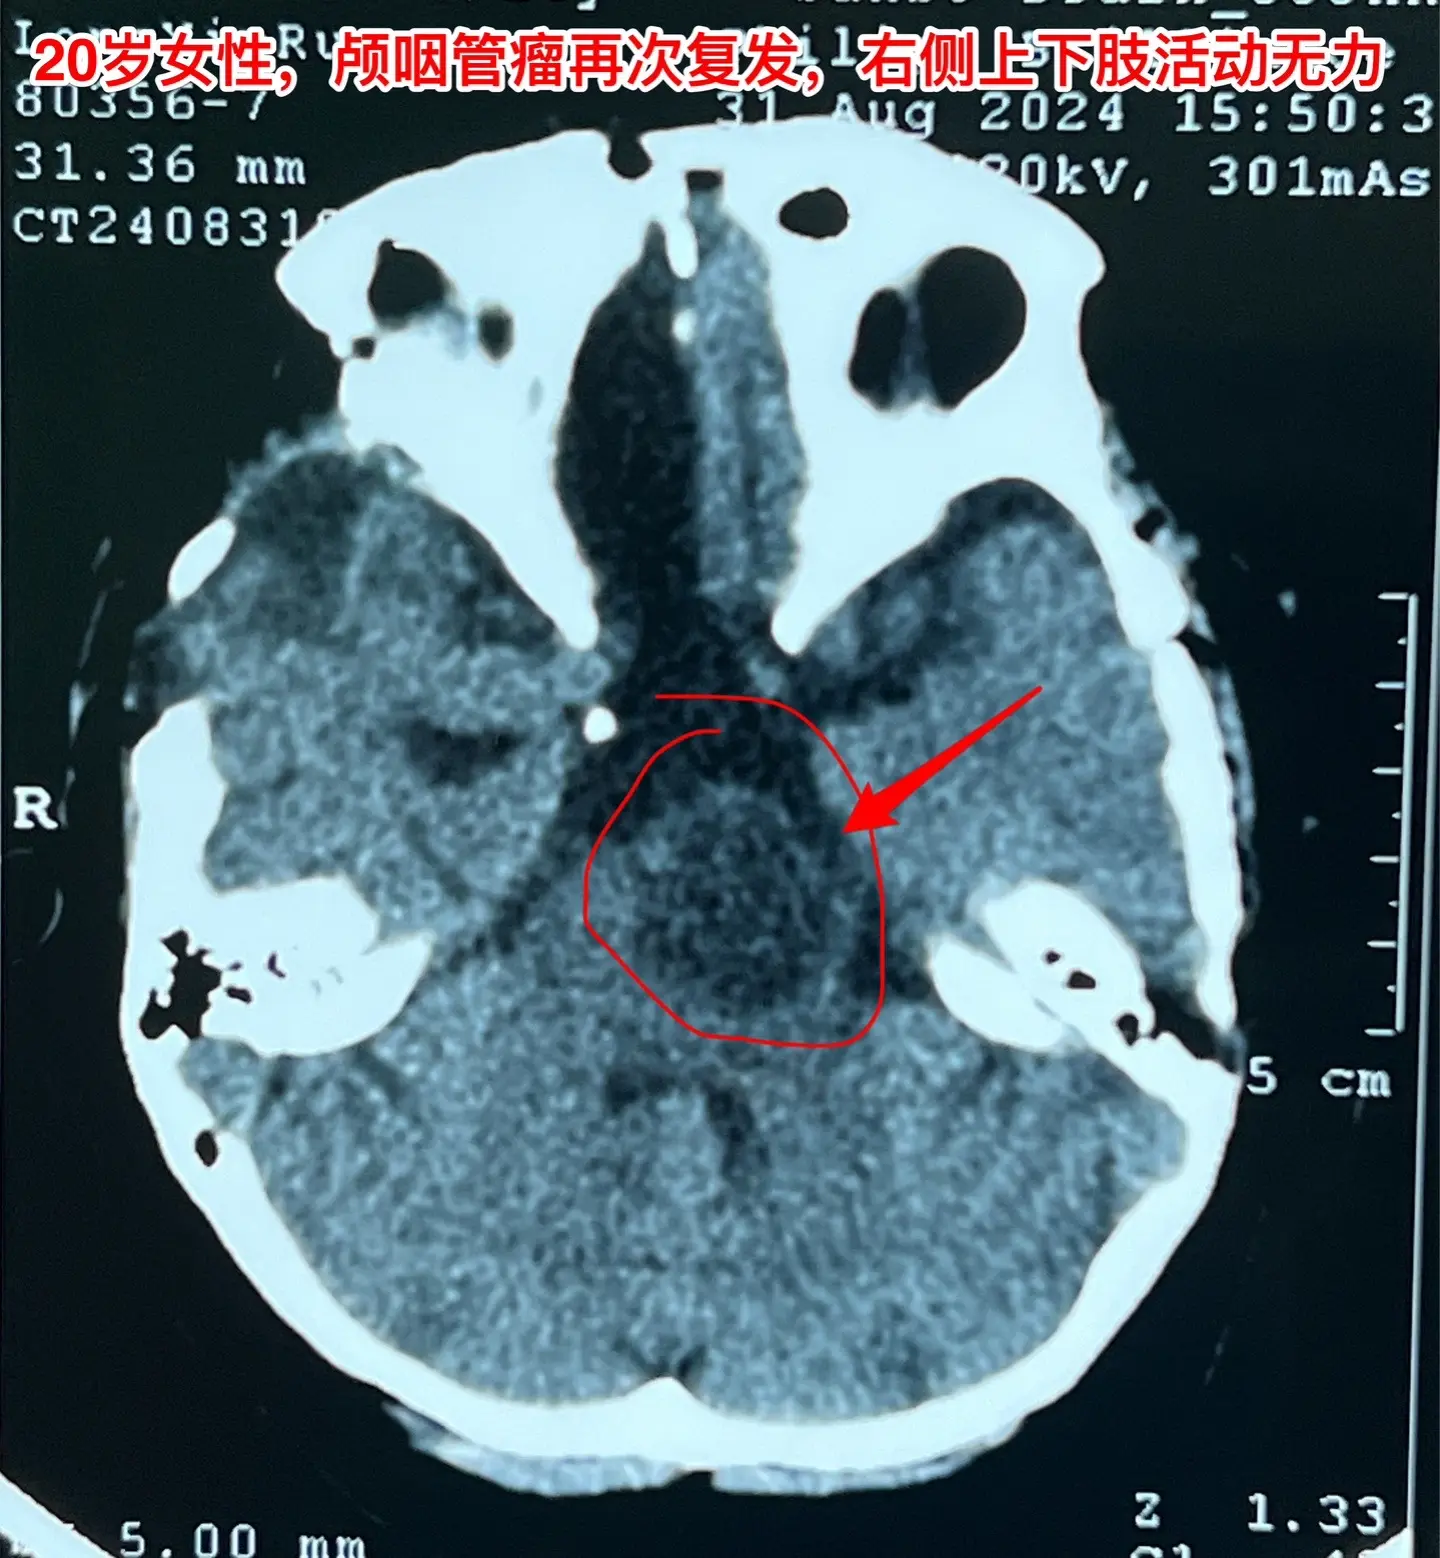

颅咽管瘤第七次开颅手术,恢复顺利。20岁女性,广东省东莞人。不幸的孩子,患颅咽管瘤,10年时间内第七次作手术。 第一次、第二次手术在广州市某医院作的。从2016年开始在我科先后作了四次手术。 三个月前患者出现贫血、头晕,在广东省查胃镜,发现食道静脉曲张、出血,有严重的贫血,还怀疑肝脏硬化。 今年八月患者出现左侧面部麻木、右侧上下肢活动力弱,8.24磁共振显示肿瘤复发,而且肿瘤嵌入脑干内。8.30患者来到三博脑科医院住院,还能自己行走。住院后症状进展很快,不能独立行走。 9月6日为她作了手术。这是第七次开颅手术。手术中将肿瘤完全切除。 虽然患者体质很弱,令人惊奇的是,术后她居然恢复很顺利,精神状态好,右侧上下肢无力症状明显改善,一天比一天好,现在能独立行走。很快就能出院了。但愿肿瘤不再复发了!